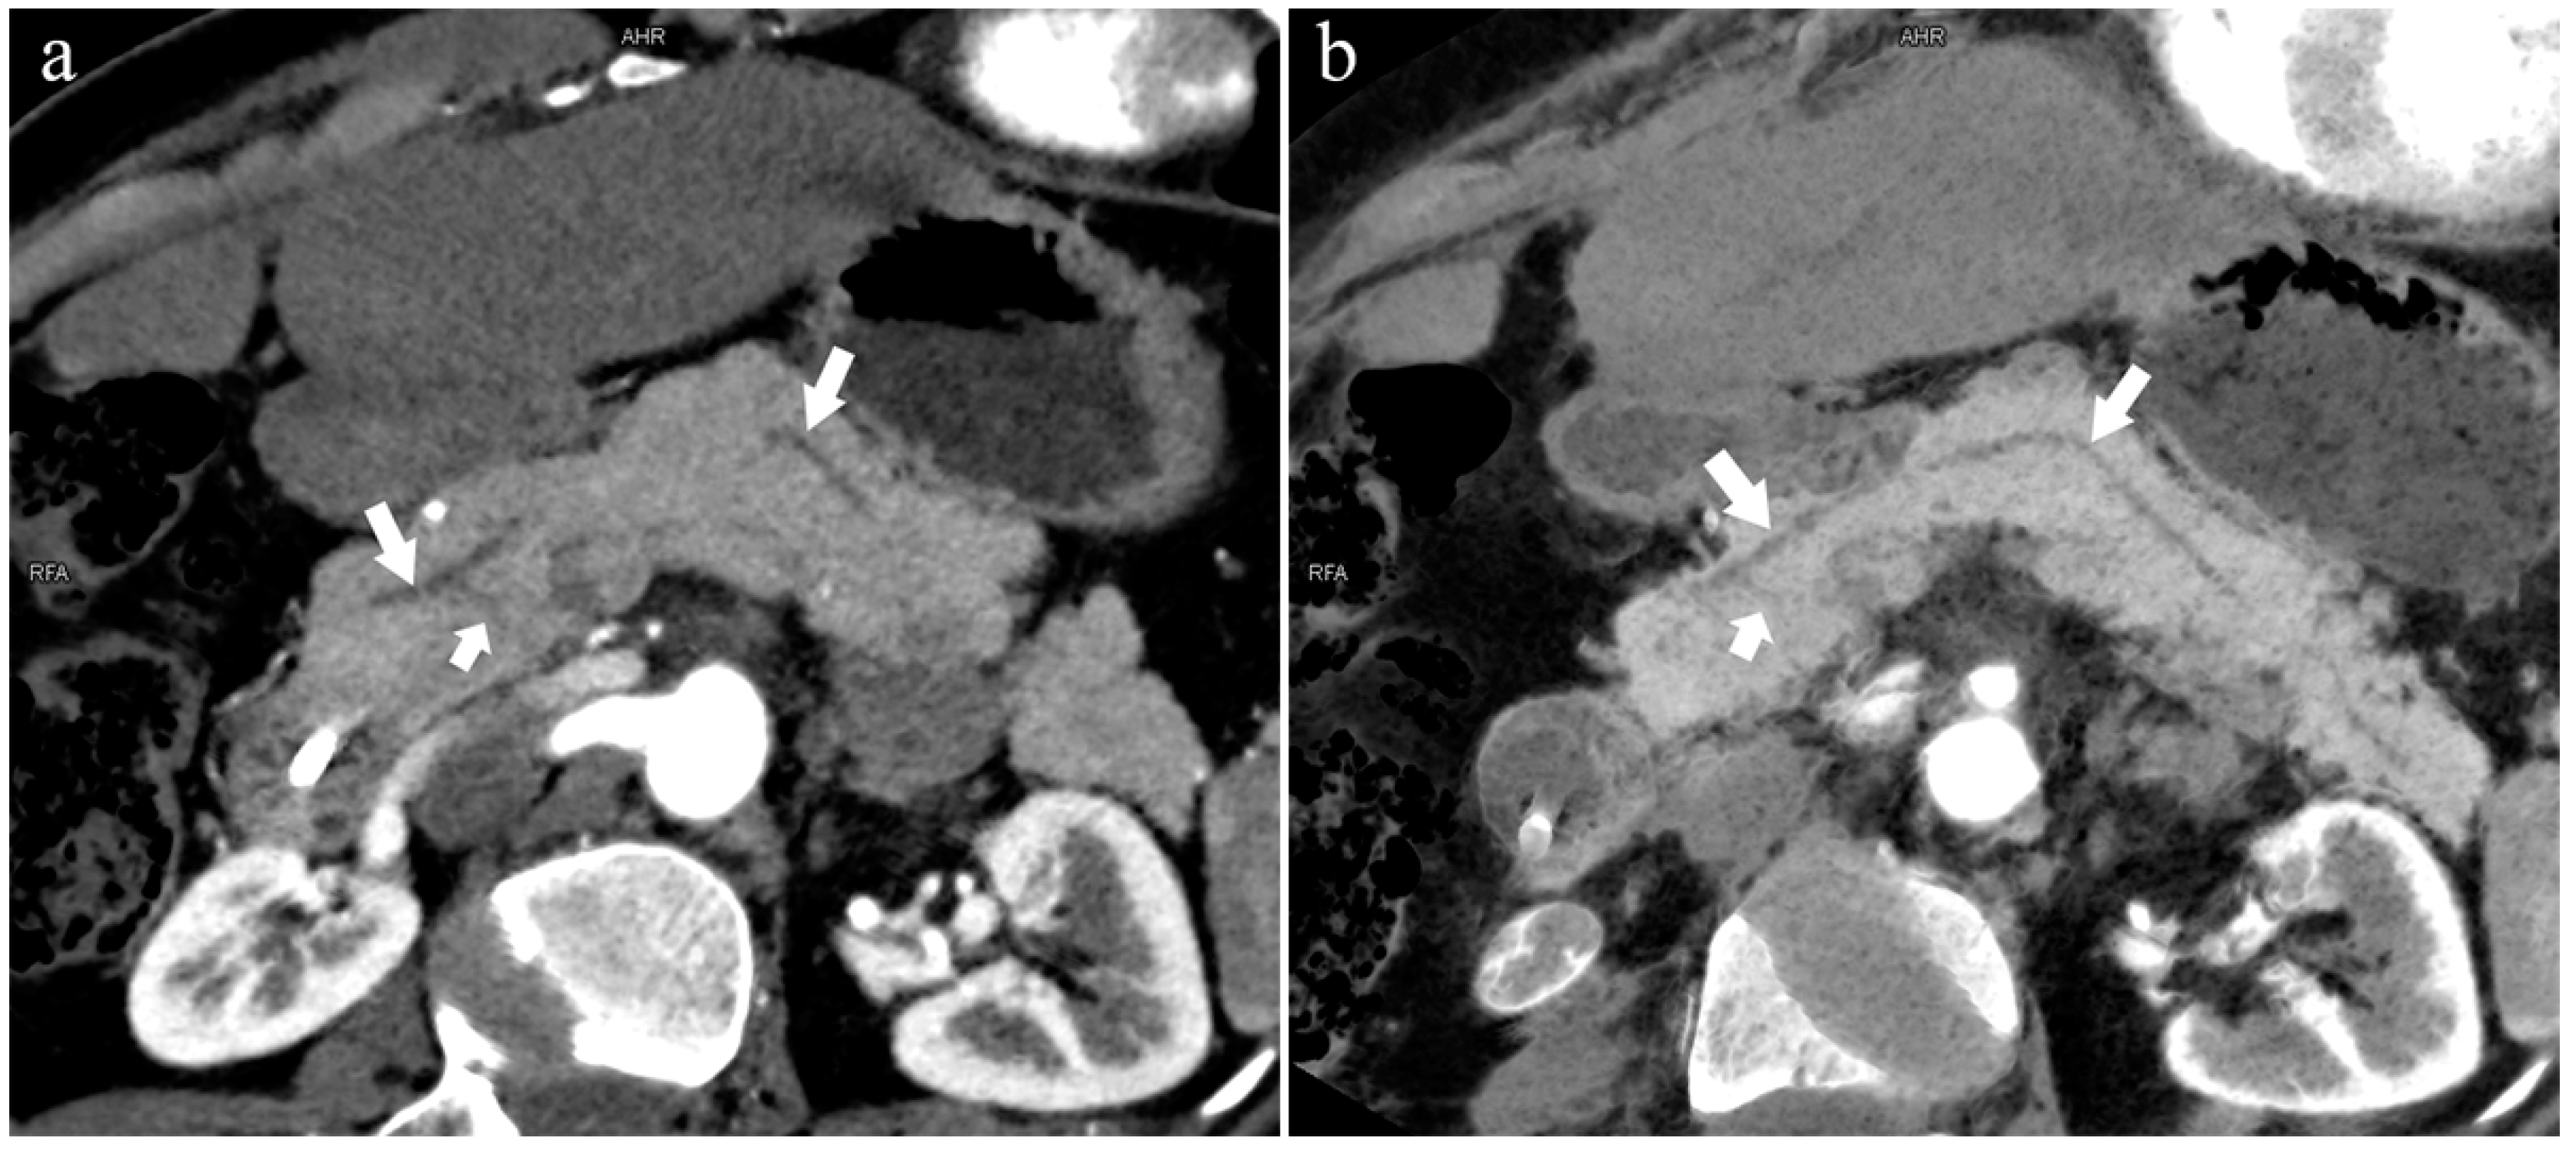

4.4. Comparison of the Sharpness of the Pancreatic Duct System between DECT and MRCP Images

5.4. Comparison between Low-keV DECT and MRCP